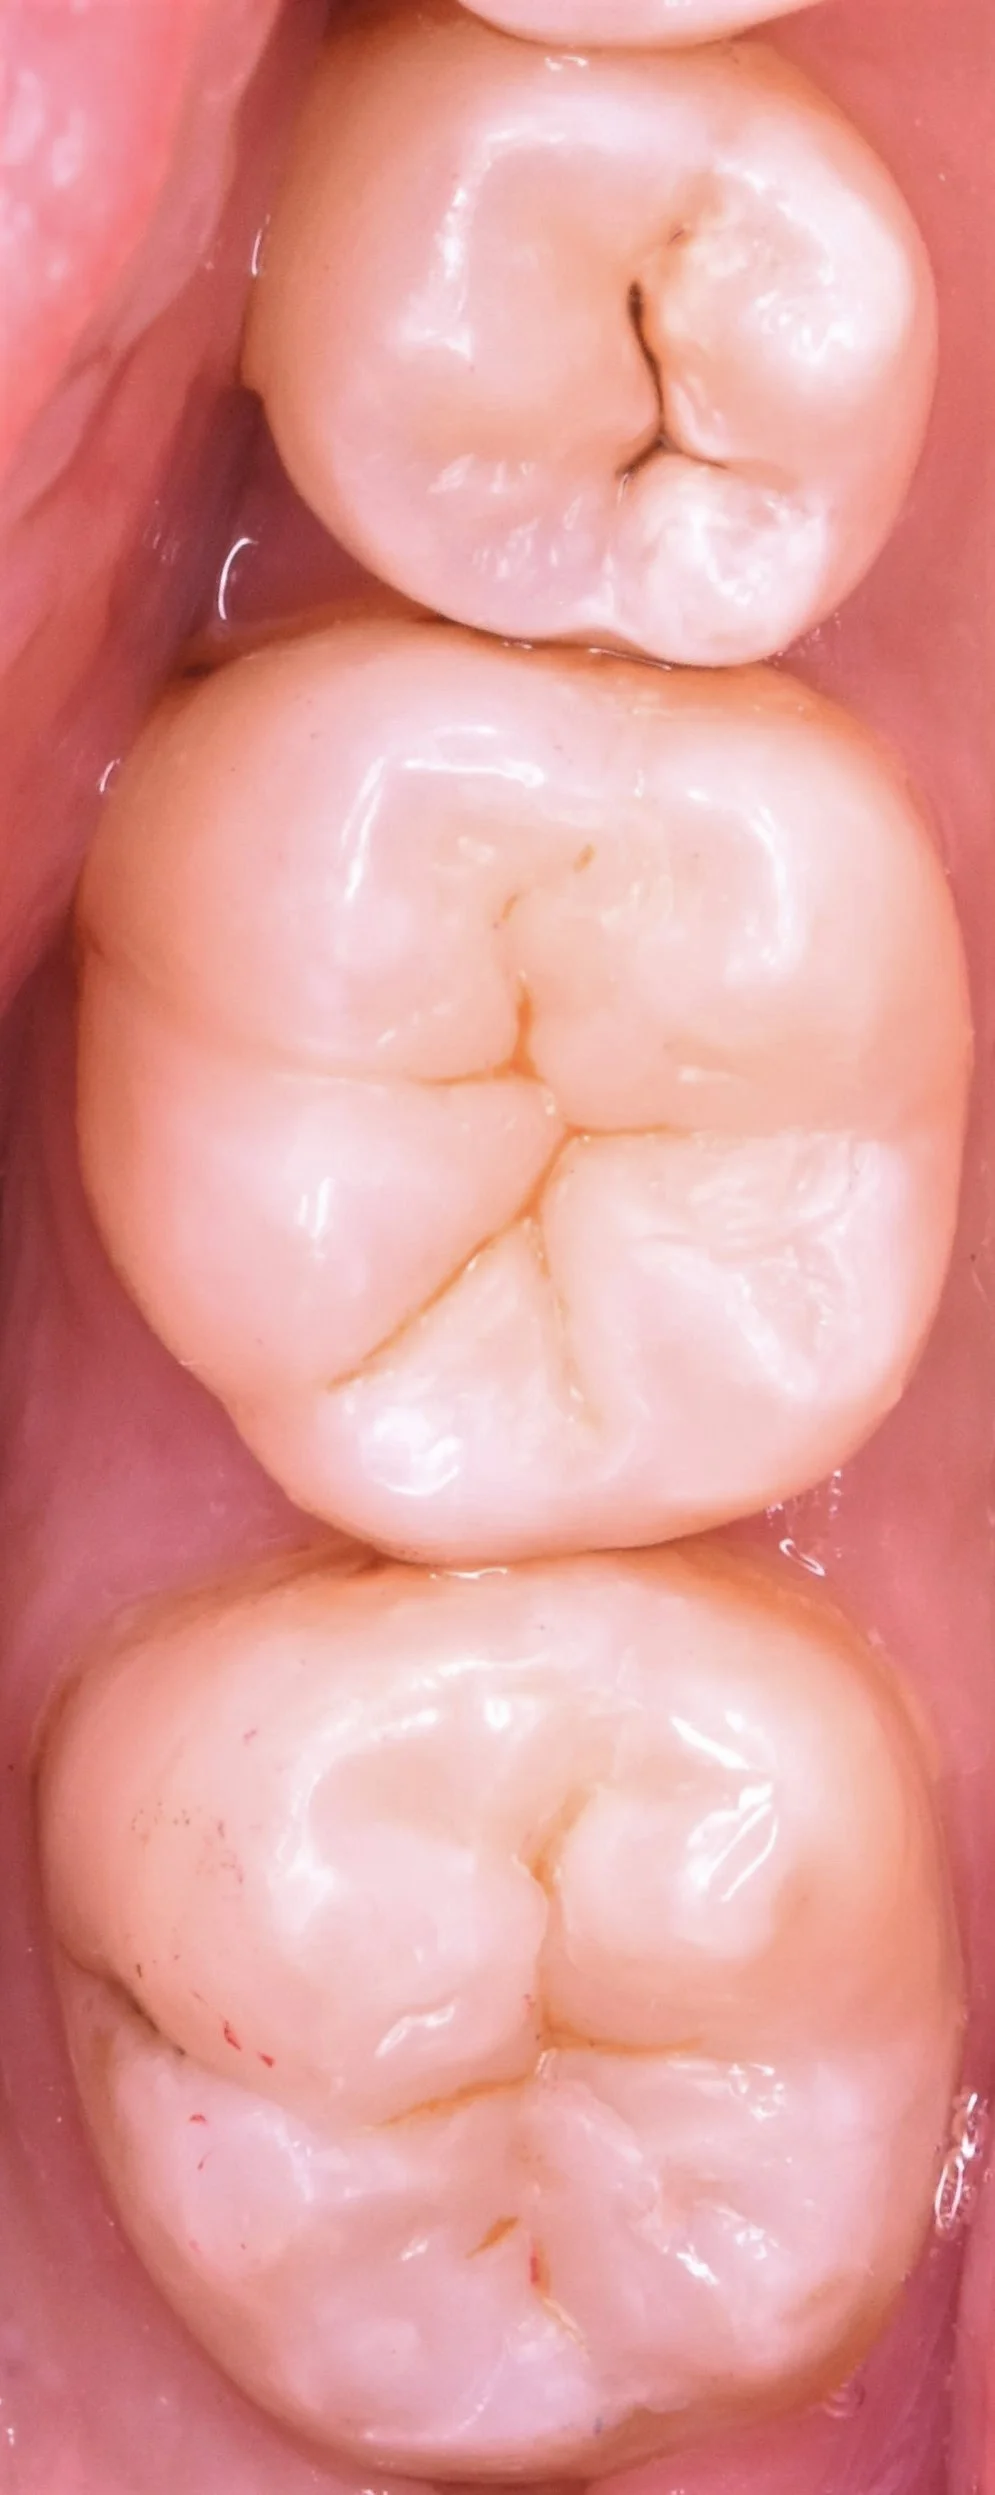

そして詰め終わったのがこちらになります。

自然な形態と色味に仕上げることができたかと思います。

詰めた個所が歯の乾燥により分かりやすくなってしまっていますが、1週間ほどすれば色はあってきてもう少し分かりづらくなってくるはずです。

術前術後の写真がこちらになります。

私がほぼ初手の介入だったということもあり、非常に多くの歯を温存できたかと思いますので、かなりの長期予後が期待できるかと思います。

今後も定期検診を通して、お口の中の健康を管理させていただきますね!